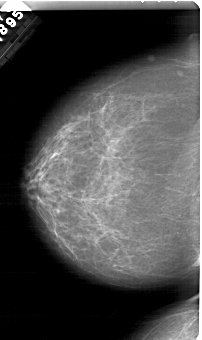

A_2001_1.RIGHT_MLO